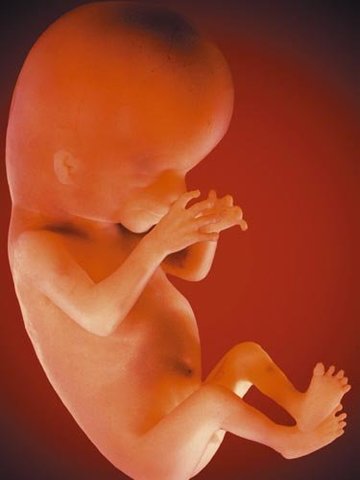

• TERCERA ETAPA

TERCERA ETAPA

Llamada fetal, es la más larga y se extiende desde el terer mes hasta el nacimiento. Al embrión se lo llama feto. Los esbozos de los órganos, comienzan a desarrollarse para poder, a medida que crece el feto dentro del útero materno, realizar las funcioes que le permitirá al recien nacido vivir en forma independiente.

• 16 SEMANA

16 SEMANA

la longitud fetal es de 16cm. y pesa de 100 a 120gramos.La cara tiene rasgos individuales propios. Aparecen los esbozos de las glándulas sebáceas en la pared de los folículos pilosos. El feto puede moverse dentro del líquido amniótico, curvando su cintura, rodando sobre sí mismo. Los movimientos fetales pueden ser percibidos por la madre.